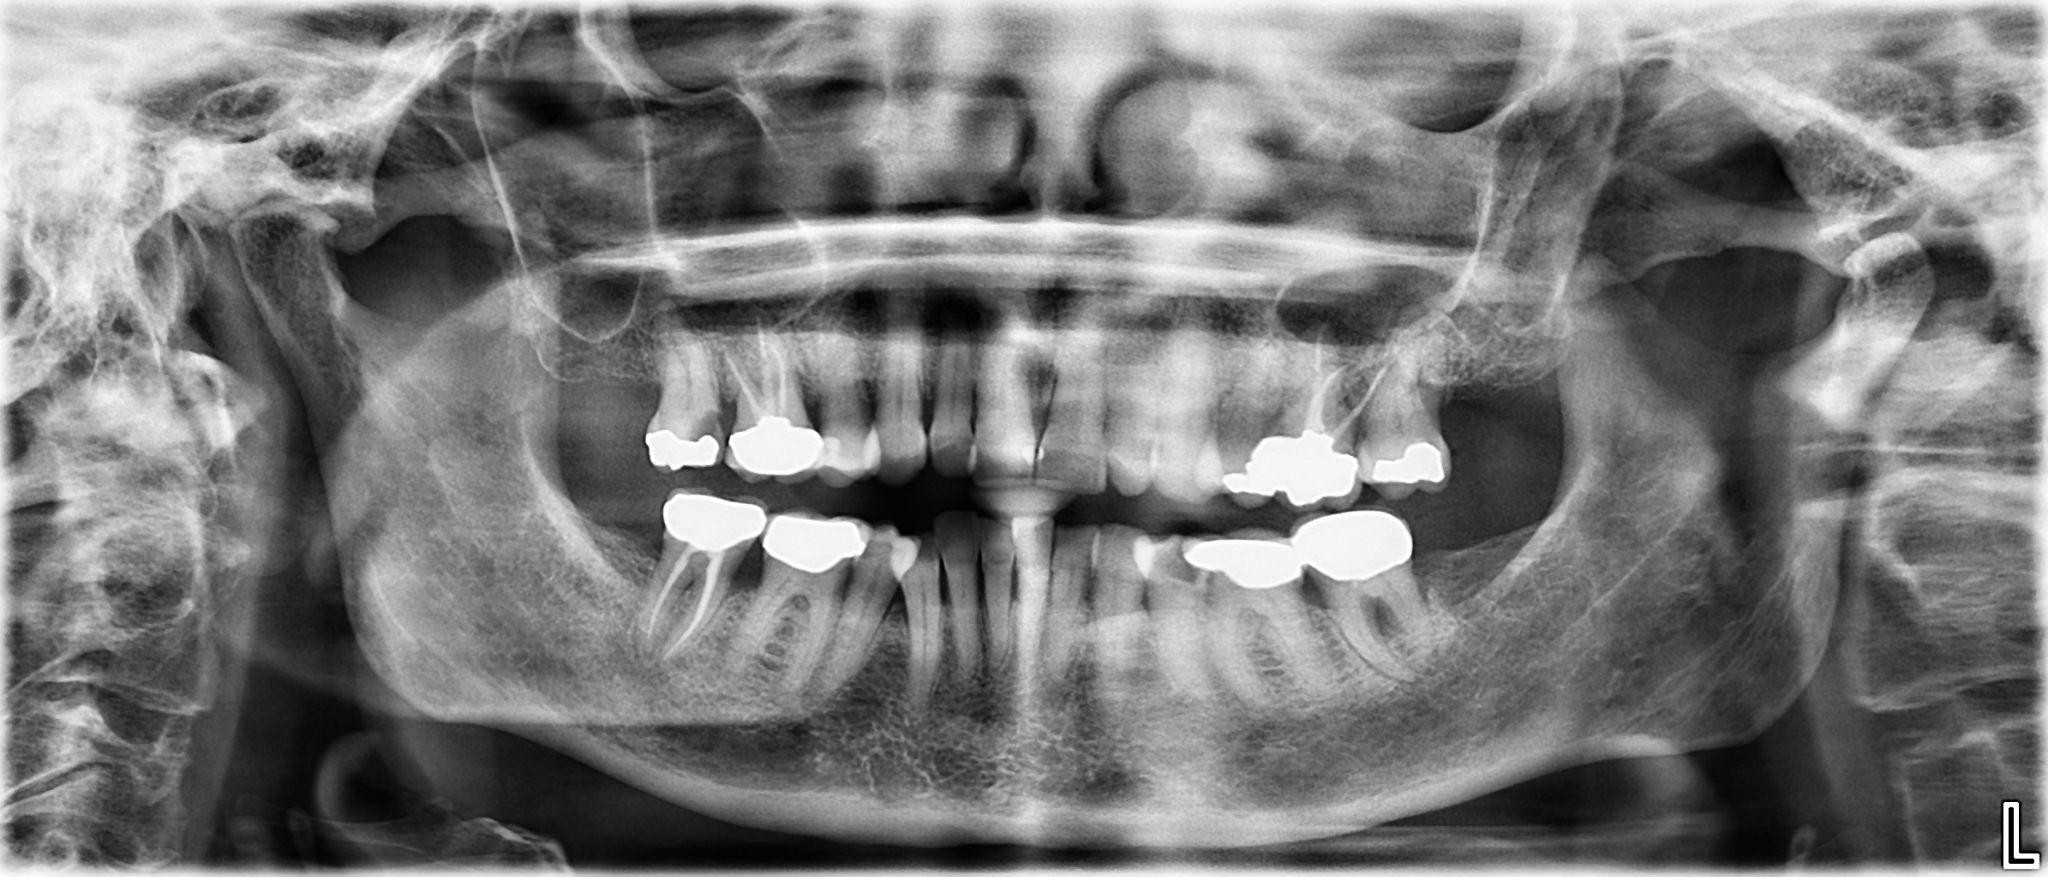

10 / 25

10. What option cannot be selected for the first quadrant of this panoramic X ray?

11 / 25

11. What option cannot be selected for the second quadrant of this panoramic X ray?

12 / 25

12. What option cannot be selected for the third quadrant of this panoramic X ray?

13 / 25

13. What option cannot be selected for the forth quadrant of this panoramic X ray?

14 / 25

14. What option cannot be selected for the upper jaw of this panoramic X ray?

15 / 25

15. What option cannot be selected for the lower jaw of this panoramic X ray?